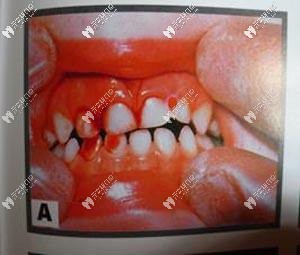

牙震蕩和磕掉牙一樣,都屬于牙齒受到外力作用出現(xiàn)的損傷。不同的是,牙齒磕掉了,你肯定一邊哭一邊沖去醫(yī)院,然而如果是碰上了牙震蕩,表面上看牙齒本身一點(diǎn)毛病都沒(méi)有,躺槍的是牙髓神經(jīng)和牙周組織,要說(shuō)癥狀,可能會(huì)出現(xiàn)牙齒輕微的叩痛、牙齦邊緣出血等。

輕度牙震蕩表現(xiàn):從外觀(guān)來(lái)看一般沒(méi)有太多異樣,咬合時(shí)有輕微不適感。? ??

正常的牙齒狀態(tài)

重度牙震蕩表現(xiàn):牙齒有輕度或中度的松動(dòng),咬合時(shí)有明顯的疼痛感,牙冠出現(xiàn)粉紅色。? ??